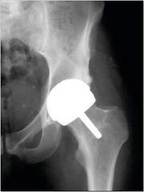

Hip Resurfacing is generally offered to younger

more active patients with good bone quality.

The advantages reported are earlier recovery

times for patients and preservation of bone in

the femur for further operations if required. The

potential disadvantages are the risk of hip

fracture and increased metal ion levels in the

body.